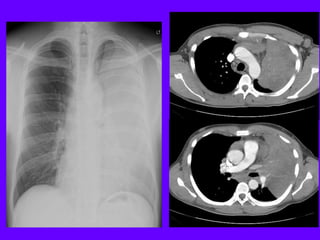

Cancer Breast

Larger right breast

Inverted nipple

Radiation Fibrosis of

Lung

Right lung smaller

Right hemithorax smaller

Paramediastinal fibrosis

Atelectasis Right Lung

Homogenous density right hemithorax

Mediastinal shift to right

Right heart and diaphragmatic silhouette are not identifiable